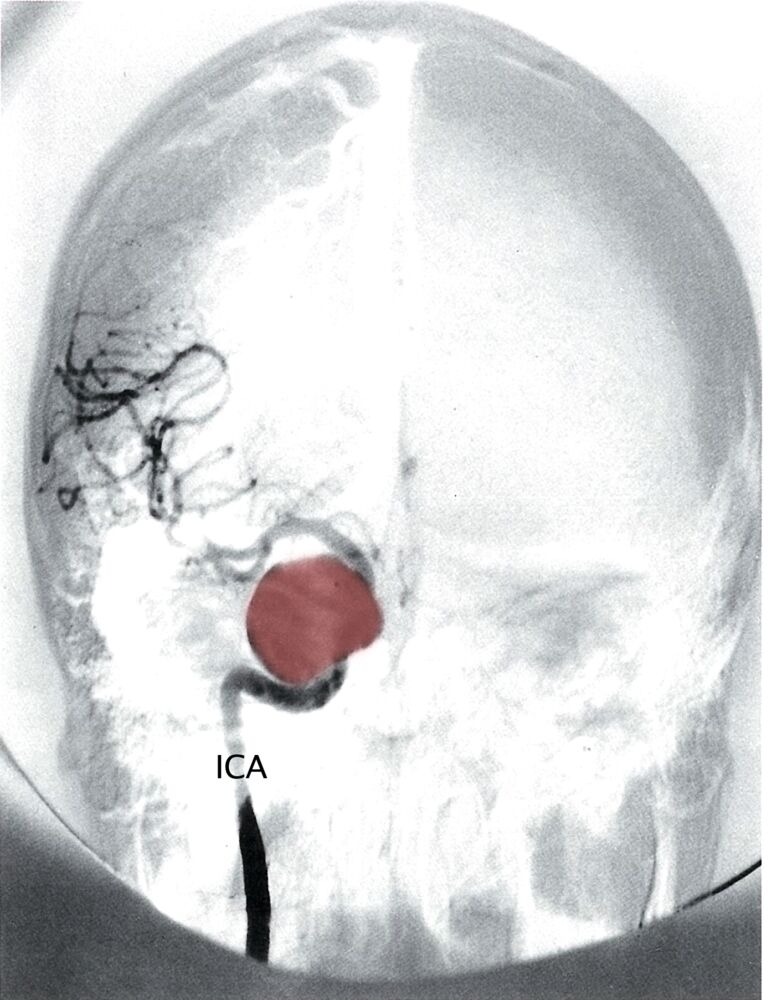

- Nontraumatic (spontaneous) SAH occurs in the setting of a ruptured cerebral saccular (berry) aneurysm or arteriovenous malformation (AVM)

- CT head without contrast (hyperdensities in the suprasellar cisterns extending peripherally)